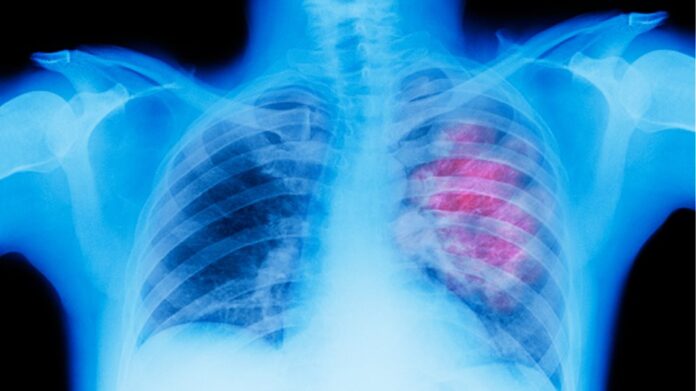

Η διάγνωση του καρκίνου του πνεύμονα σε πρώιμο στάδιο με αξονική τομογραφία χαμηλής δόσης βελτιώνει σημαντικά το ποσοστό επιβίωσης μακροπρόθεσμα, σύμφωνα με μεγάλης κλίμακας μελέτη ερευνητών της Ιατρικής Σχολής του Mount Sinai, που δημοσιεύεται στο περιοδικό Radiology.

Περισσότεροι από τους μισούς ασθενείς με καρκίνο του πνεύμονα πεθαίνουν εντός ενός έτους από τη διάγνωσή τους, καθιστώντας τον την κύρια αιτία θανάτου από καρκίνο, καθώς μέχρι να εμφανιστούν τα συμπτώματα είναι συχνά πολύ αργά. Μόνο το 16% των καρκίνων του πνεύμονα διαγιγνώσκονται σε πρώιμο στάδιο. Αν και οι θεραπείες των προχωρημένων καρκίνων με στοχευμένη θεραπεία και ανοσοθεραπεία έχουν εξελιχθεί πολύ, το καλύτερο εργαλείο κατά των θανάτων από καρκίνο του πνεύμονα είναι η έγκαιρη διάγνωση πριν από την εμφάνιση συμπτωμάτων, επισημαίνουν οι συγγραφείς της μελέτης.

Στην έρευνα μελετήθηκαν 1.257 συμμετέχοντες που διαγνώστηκαν με καρκίνο του πνεύμονα και εξετάστηκαν τα ποσοστά επιβίωσής τους σε χρονικό διάστημα 20 ετών. Από αυτούς τους ασθενείς, το 81% είχε νόσο σταδίου Ι, δηλαδή έναν πολύ μικρό όγκο που δεν έχει εξαπλωθεί στους λεμφαδένες. Το ποσοστό μακροχρόνιας επιβίωσής τους ήταν 87%. Εάν η διάγνωση γινόταν στο πρωιμότερο στάδιο Ι η μακροχρόνια επιβίωση θα ήταν 95%.

Η ομάδα εμπειρογνωμόνων «Ομάδα Εργασίας Προληπτικών Υπηρεσιών των ΗΠΑ» συνιστά ετήσιο έλεγχο με αξονική τομογραφία χαμηλής δόσης για τον καρκίνο του πνεύμονα σε ενήλικες 50-80 ετών, οι οποίοι έχουν ιστορικό καπνίσματος 20 ετών (σ.σ. ως μονάδα μέτρησης υπολογίζεται το κάπνισμα ενός πακέτου την ημέρα για 20 χρόνια) και καπνίζουν σήμερα ή έχουν διακόψει το κάπνισμα τα τελευταία 15 χρόνια.